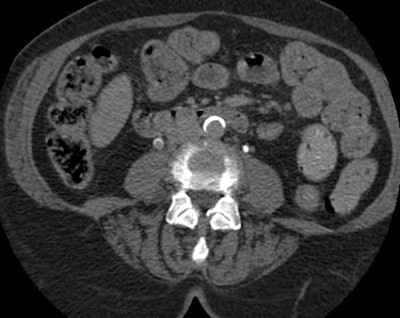

| Transitional cell cancer of the right upper ureter. Above, axial excretory-phase CT showing soft-tissue filling defect in the upper third of the ureter. Below, coronal thin-slab maximum intensity projection showing characteristic signs of ureteral transitional cell carcinoma. Images courtesy of Dr. Nigel Cowan. |